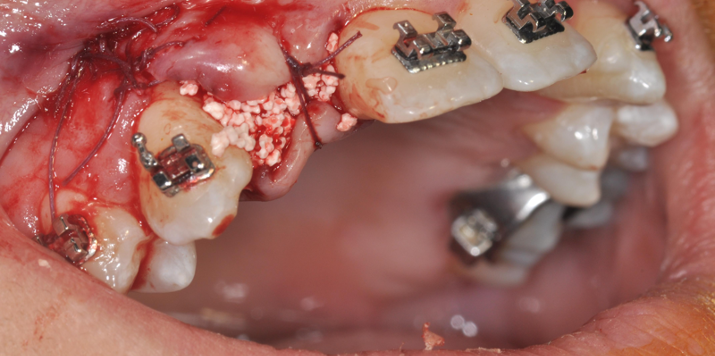

→ Pose du ou des implants

Durant cette étape, le praticien pose les implants dentaires pour remplacer les racines manquantes. À l’issue de cette intervention, vous sentirez des implants couverts par la gencive, et qu’ils sont mis en “nourrice” : cela permet à l’os de cicatriser autour des implants.

L’implant dentaire est placé dans la mâchoire sous anesthésie locale dans la majorité des cas, parfois sous anesthésie générale.